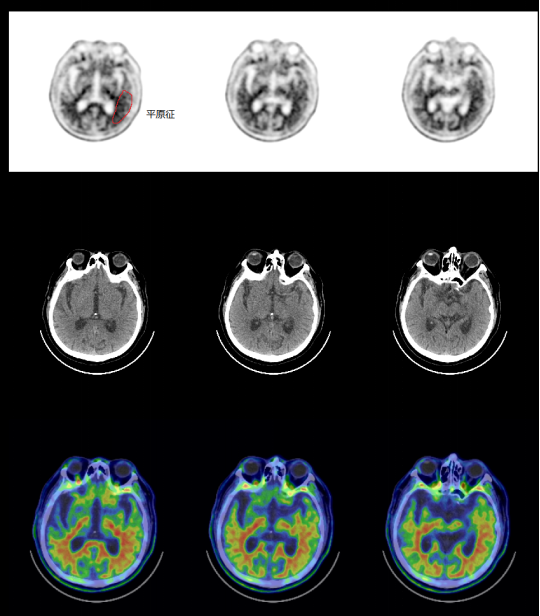

18F-AV45PET图像

▲冠状位可见“夏树征”

▲横断位颞枕叶可见“平原征“

▲  矢状位可见“亲吻征”

▲矢位图

▲冠位图

▲轴位图

AβPET(18F-AV45)图像判读结果

大脑皮质内弥漫性放射性摄取增高,灰白质分界不清,以双侧额叶、顶叶、颞叶、后扣带回等脑区为明显。额叶皮质SUVmean:2.0,顶叶皮质SUVmean:1.54,颞叶皮质SUVmean:1.78,后扣带回SUVmean:1.78,枕叶皮质SUVmean:2.28,小脑皮层SUVmean:0.88。大脑皮质 Aβ(β-淀粉样蛋白)异常沉积,考虑Aβ PET显像阳性。